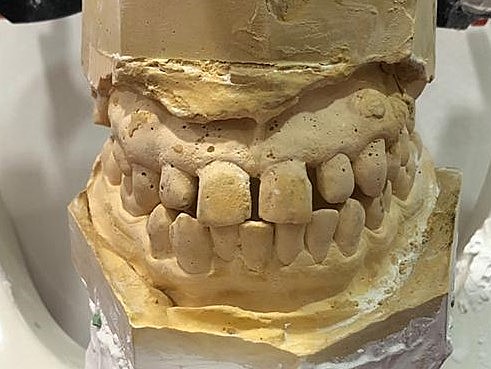

• Toma de modelos y fotografías intraorales

Toma de modelos y fotografías intraorales

Se realizó la toma de modelos como protocolo para una correcta valoración y estudio del paciente; como también la toma de fotografías de estudio intraorales del maxilar y mandíbula. En estas fotografías intraorales se encontró que el paciente tiene el frenillo labial superior extendido. Lo que ha provocado el diastema en el paciente.

• Diseño de prótesis removible

Diseño de prótesis removible

Con una cucharilla comercial y alginato se toman modelos de estudio para poder elaborar el diseño de la prótesis removible.